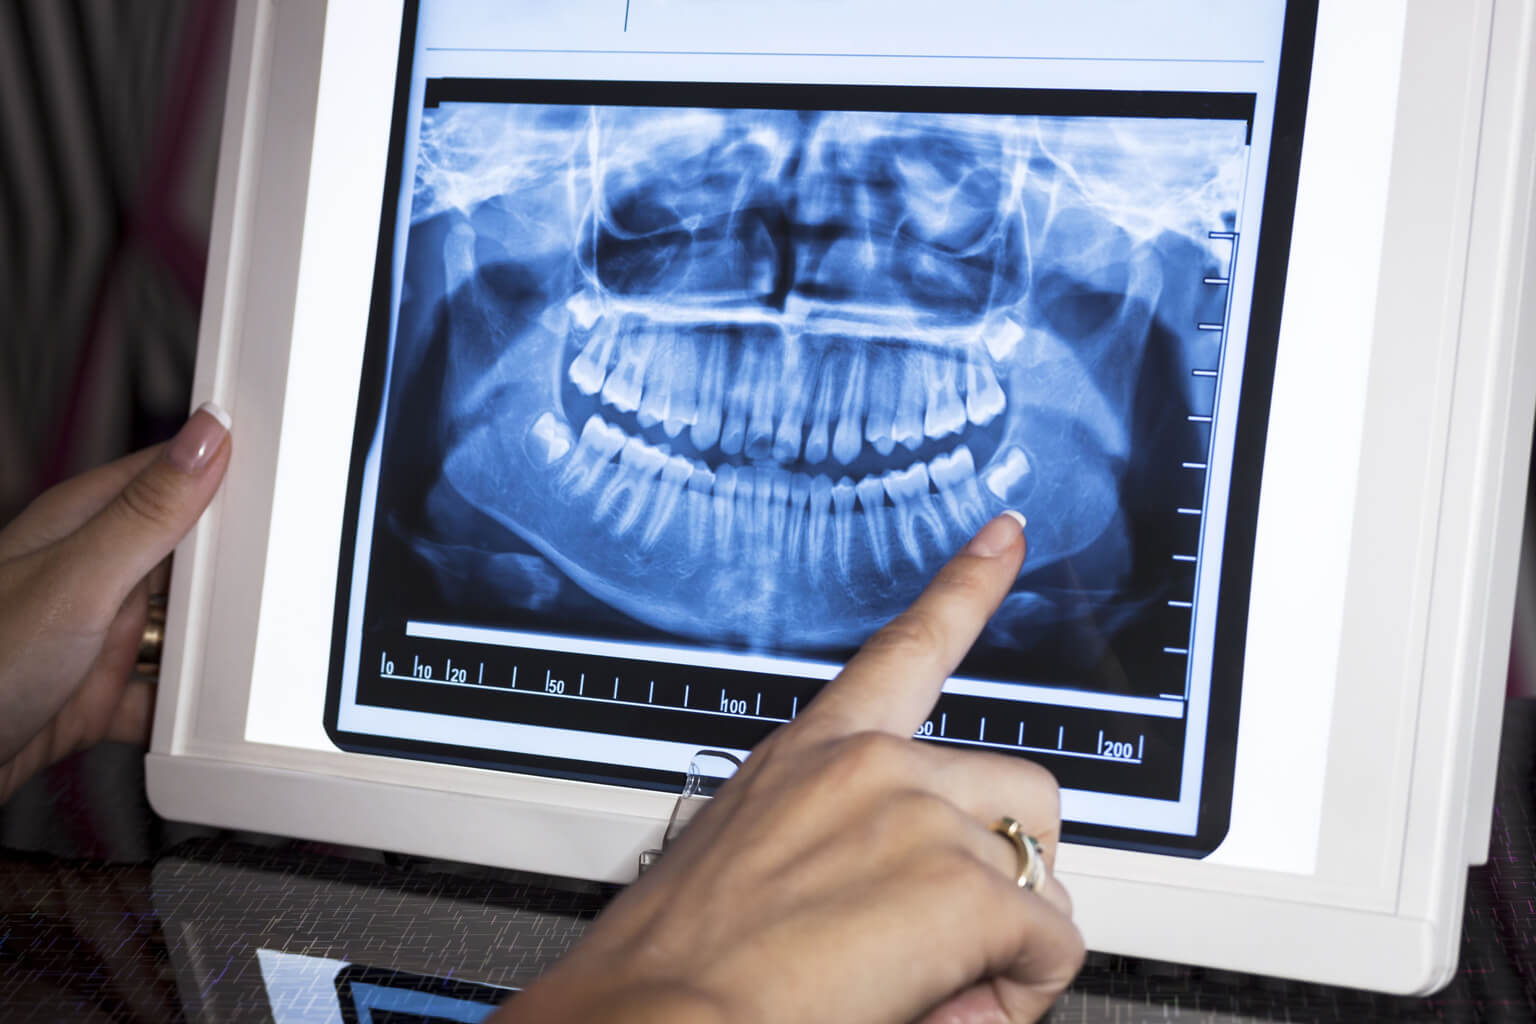

What is a Dental X-Ray?